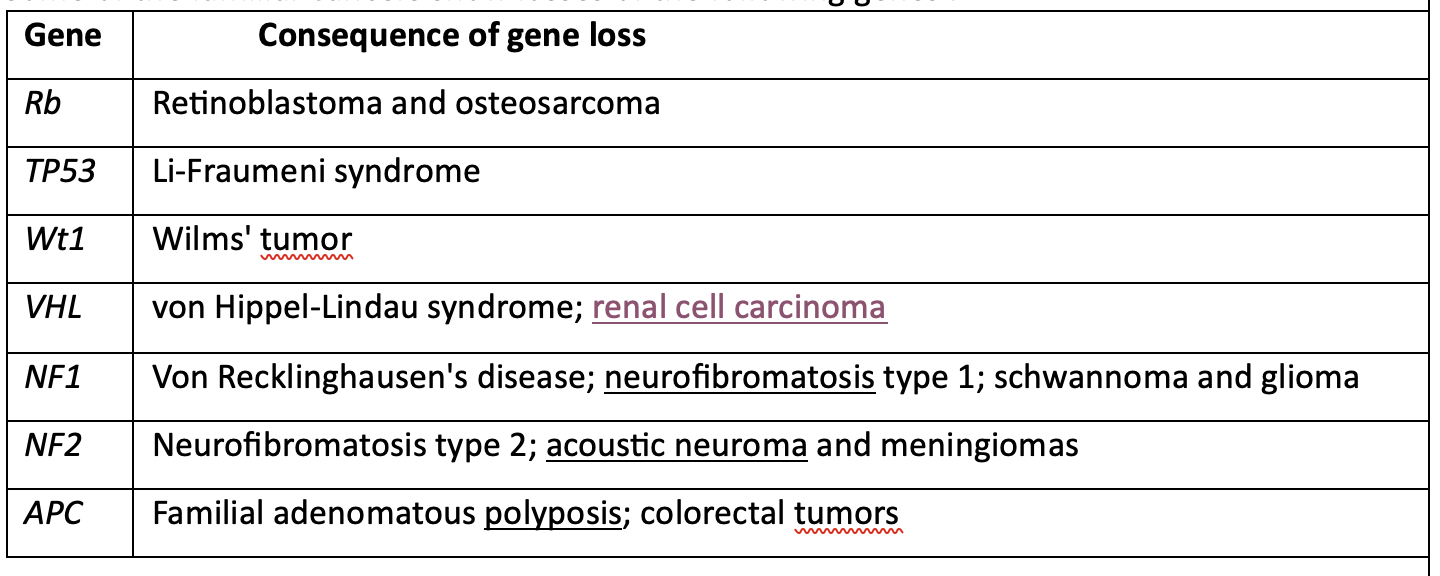

Some of the familial Cancers show losses of the following genes :

Gene Consequence of gene loss